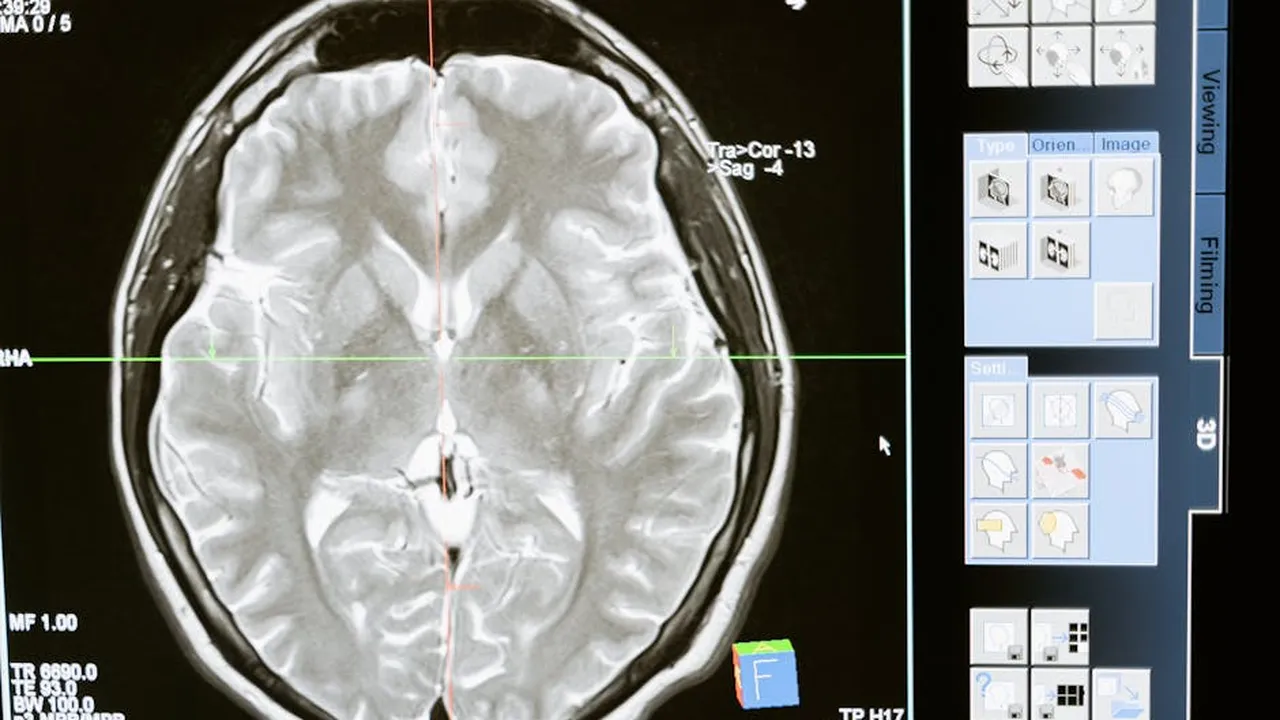

To diagnose TIP, doctors use a combination of physical examinations and imaging tests such as X-rays, CT scans, and MRI scans. The American Spinal Injury Association (ASIA) Impairment Scale is often used to classify the severity of the spinal cord injury and resultant paralysis.